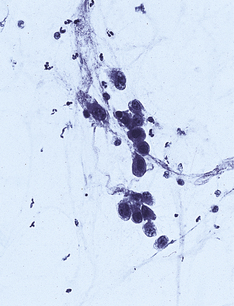

Pneumocystis jiroveci

Alveoli are filled with a bubbly pink exudate. Round or crescent-shaped organisms are seen using a silver impregnation stain. There may also be diffuse alveolar damage.